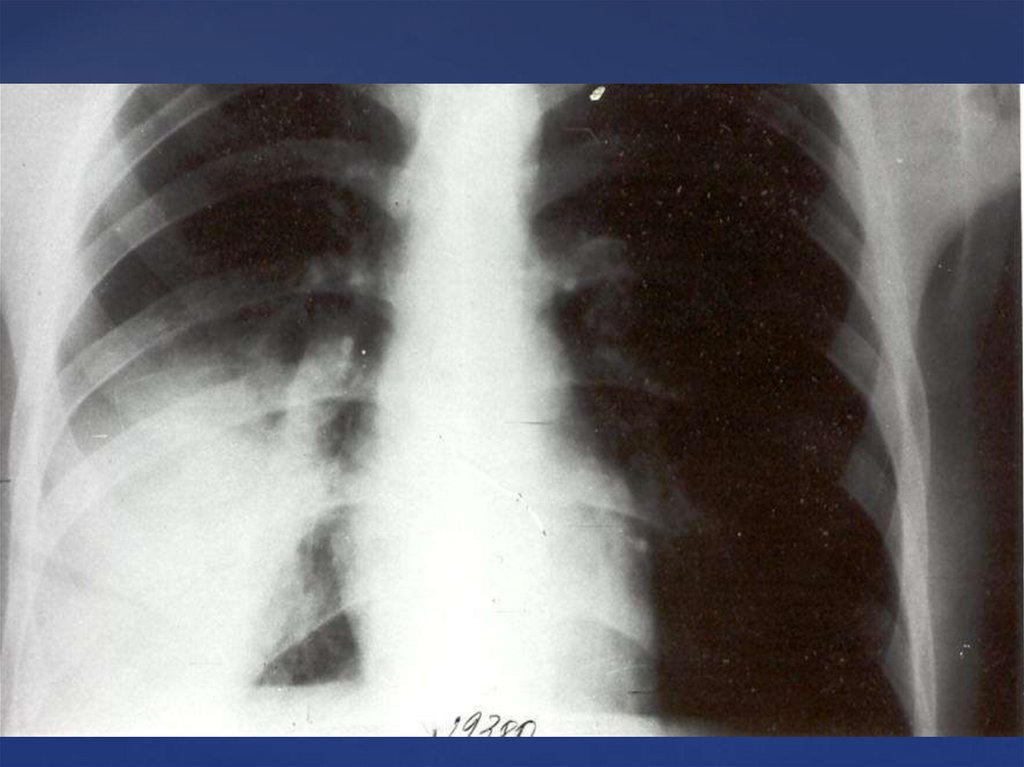

Рентгенография — очаги воспалительной инфильтрации.

Рентгеноскопия – деформация или нечеткость корня легких.

Рентген-исследование. Периферический рак обычно локализуется в

передних сегментах верхних долей легких. Рентгенологические

проявления его во многом зависят от размеров: она проявляется

очагом затемнения неправильной округлой формы. Если рак средних и

больших размеров, то имеет более правильную шаровидную форму.

Довольно часто, при периферическим раке видна «дорожка» к корню

легкого, обусловленная лимфангиитом.